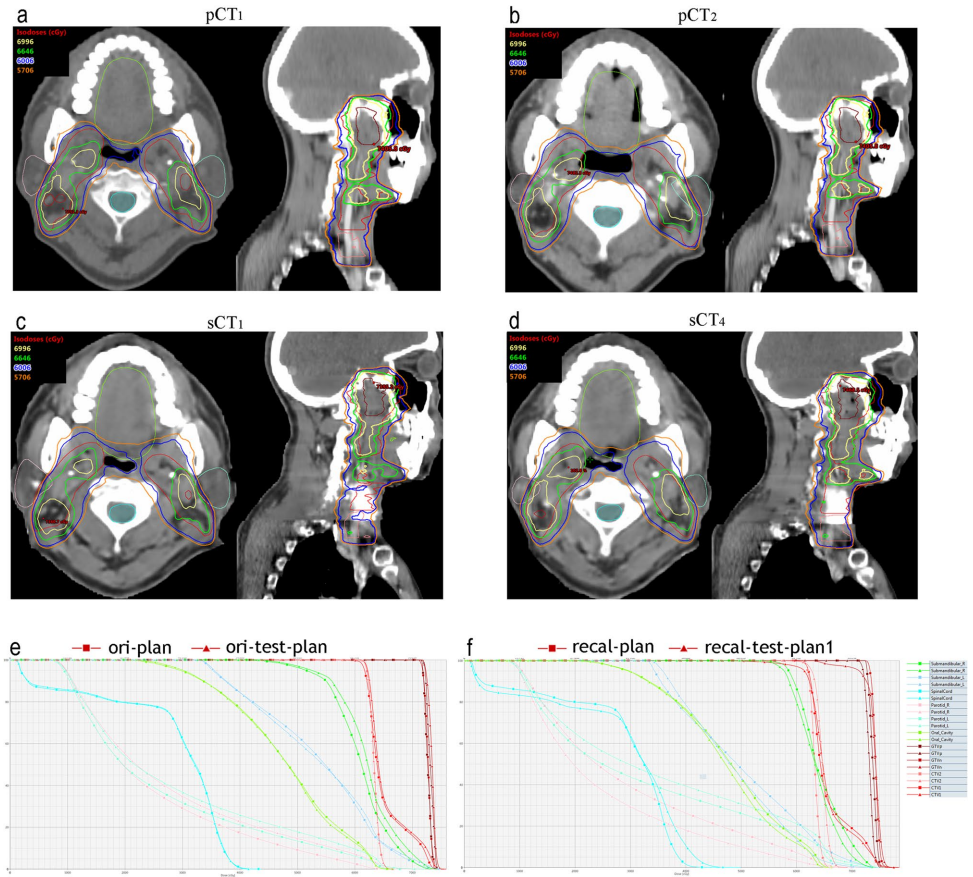

研究纳入16例II-III期NPC患者,采集初始(pCT1)和自适应(pCT2)计划CT及每周CBCT。采用ArcherQA平台实现三大核心步骤:(1)基于Cycle-GAN生成sCT;(2)改进神经网络自动分割靶区(GTVp/GTVn)和危及器官(腮腺/颌下腺);(3)GPU蒙特卡洛剂量重计算。对比分析sCT与金标准pCT的剂量差异,并通过Spearman相关性评估体积变化与计划调整的关联。

剂量计算一致性

sCT剂量差异具有结构特异性:CTV1 D99偏差-1.54Gy,GTVn D99偏差-1.44Gy。右侧腮腺平均剂量差异达-1.94Gy(p<0.05),与体积变化显著相关(r=0.72)。自适应计划(adap-plan)较非调整计划(recal-plan)显著降低OAR剂量,如左侧腮腺MD减少3.58Gy(p<0.05),验证了sCT指导ART的临床价值。

sCT成功捕捉到治疗中关键变化:CTV1体积缩减16.1%,GTVn缩减63.2%,右侧腮腺体积减少26.3%。这些变化与离线ART计划调整高度相关(r>0.78),证实sCT可替代CT监测解剖演变。